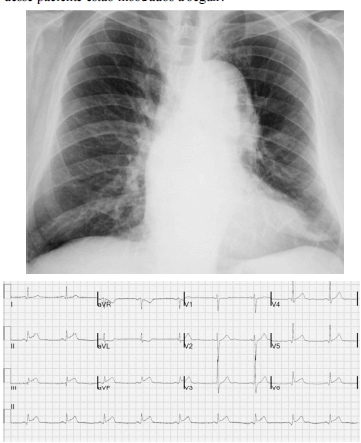

Um paciente de 68 anos de idade e hipertenso apresentava dor torácica lancinante na parede anterior com irradiação para a região cervical, de forte intensidade e sem alívio com analgésicos comuns havia duas horas. No exame físico, ele se encontrava sudorético e acianótico, com saturação de oxigênio em ar ambiente de 90%, pressão arterial de 182 mmHg × 112 mmHg e frequência cardíaca de 88 bpm. Apresentava ritmo cardíaco regular em dois tempos, com sopro diastólico (+/4) no segundo espaço intercostal à direita. Os valores da troponina ultrassensível foram normais. A radiografia de tórax e o eletrocardiograma desse paciente estão mostrados a seguir.

Com relação ao caso clínico hipotético anterior, julgue o item que se segue.

Recomenda-se o uso de nitroprussiato de sódio para a redução de até 25% da pressão arterial média em uma hora.

A angiografia coronariana é o método de escolha para a confirmação diagnóstica.

A origem desse processo é explicada por ruptura de ateroma com grande atividade proteolítica, núcleo lipídico e necrótico proeminente, o que resulta na formação de um trombo sobrejacente.

A dupla antiagregação plaquetária e a heparina não fracionada devem ser iniciadas na admissão.